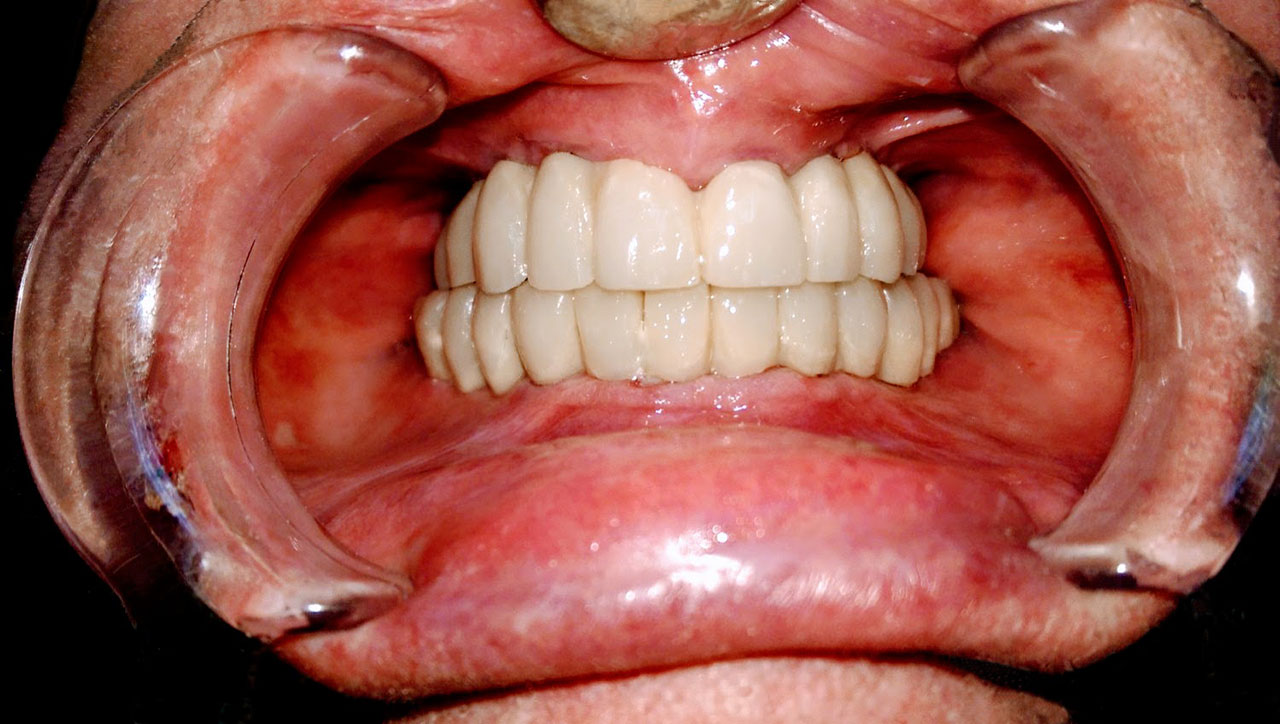

• esettanulmany-12

72 órával az alsó-felső állcsont teljes implantációs helyreállítása után, így mosolyog a páciens a beragasztott, fix hidakkal.